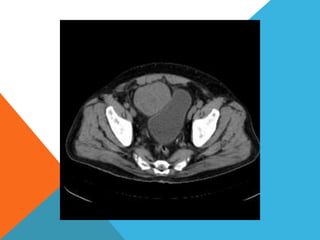

El paciente presentó síntomas de sangrado digestivo y pérdida de peso. Exámenes revelaron gastritis crónica asociada a H. pylori. Un tumor fue descubierto en una colonoscopia normal. La cirugía removió un tumor fibroide solitario, una rara neoplasia mesenquimal que usualmente crece lento y tiene bajo potencial de malignidad. El pronóstico después de la remoción quirúrgica es generalmente bueno.